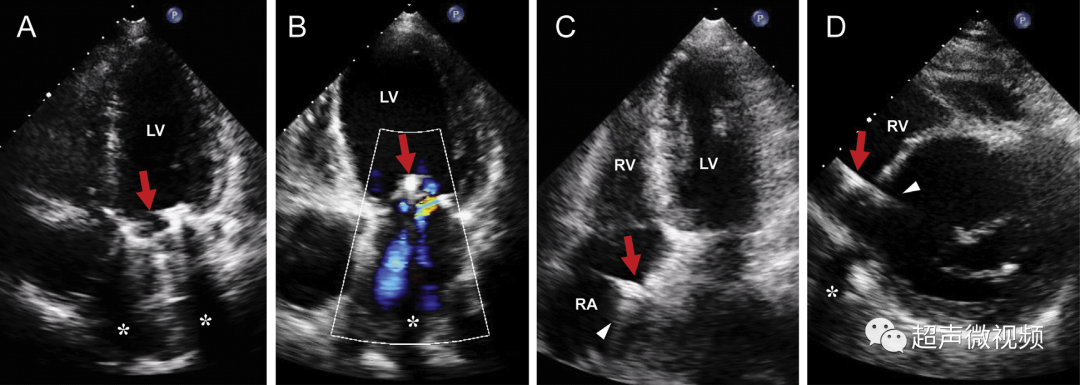

(A)人工机械二尖瓣下方的多个混响和彗尾(箭头)以及瓣环下方的两个声学阴影区域(星号)(视频 11)。(B) 植入 MitraClip 装置(箭头)远端的声学阴影(星号)。还要注意血流信号的阴影,这可能会导致低估二尖瓣反流量。(C) 右心房 (RA) (箭头) 中的起搏器导线,导线下方有线性彗尾混响 (箭头),旁瓣伪影沿径向延伸。(D) 右心室 (RV)(箭头)中的除颤器导线,具有穿过解剖边界(室间隔)的线性弧状旁瓣伪影。这不应被误解为错位(穿孔)导线进入左心室腔(视频 12)。